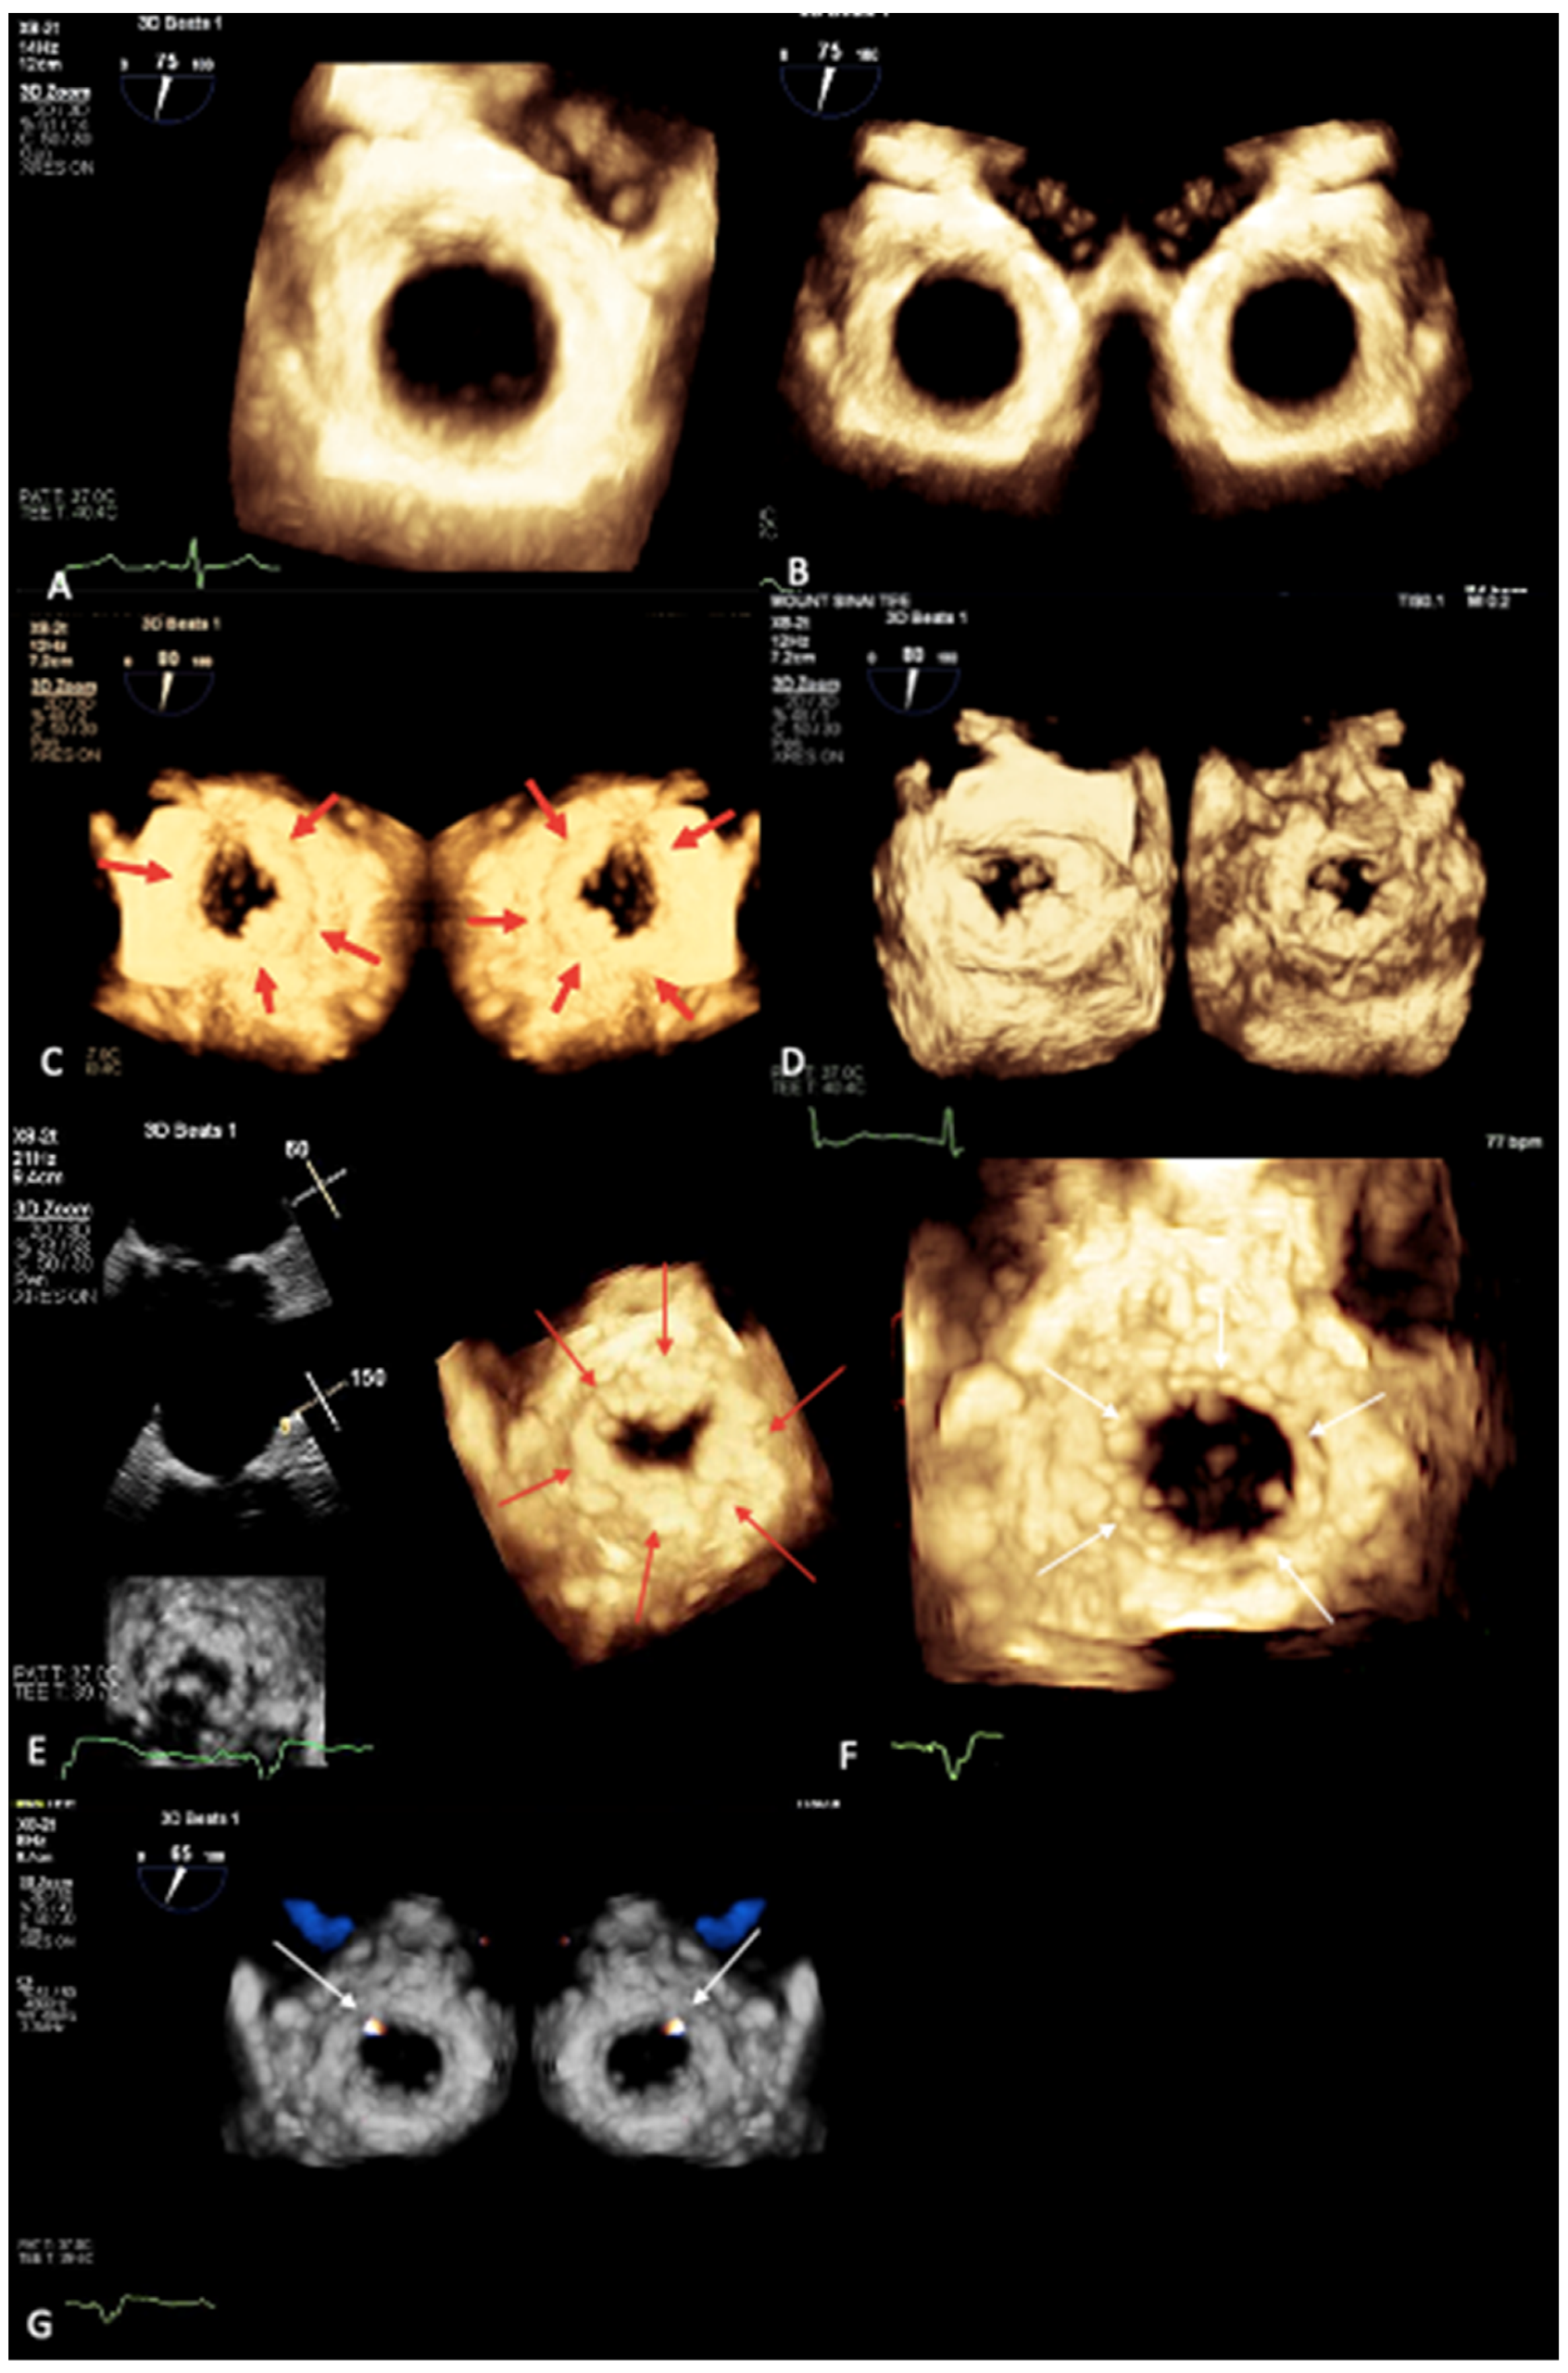

2. Mitral Annular Calcification Imaging

3. Novel 3D Echocardiographic Technique for MAC

4. Maximal Intensity Projection Map Applications

- Prandi, F.R.; Anastasius, M.O.; Zhang, L.; Tang, G.H.; Moreno, P.R.; Romeo, F.; Barillà, F.; Sharma, S.; Kini, A.; Lerakis, S. Novel Three-Dimensional Transesophageal Echocardiographic Method for Mapping Mitral Annular Calcifications. J. Am. Soc. Echocardiogr. 2022, 35, 1004–1005. [Google Scholar] [CrossRef] [PubMed]

- Prandi, F.R.; Dangas, G.D.; Kini, A.; Romeo, F.; Suleman, S.; Khera, S.; Tang, G.H.; Sharma, S.; Lerakis, S. Intraprocedural Mapping of the Mitral Calcium for Positioning and Deployment of Transcatheter Valve-in-Mitral Annular Calcification. JACC Cardiovasc. Interv. 2022, 15, 2341–2343. [Google Scholar] [CrossRef] [PubMed]